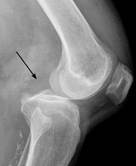

ACL Trauma

ACL Trauma Perception

“Expert” level perception of ACL trauma on knee xray exams (Segond fracture) using sparse data.